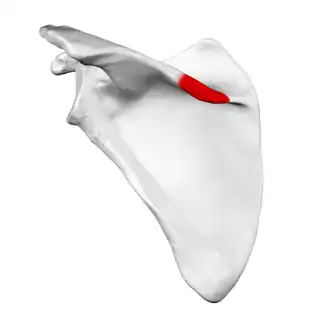

Deltoid tubercle of spine of scapula

| Deltoid tubercle (of spine of scapula) | |

Left scapula. Posterior view. Deltoid tubercle shown in red. | |

The deltoid tubercle of spine of scapula is a prominence on the spine of scapula. The spine, at lateral to the root of the spine, curves down and laterally to form a lip.[1] This lip is called the deltoid tubercle.